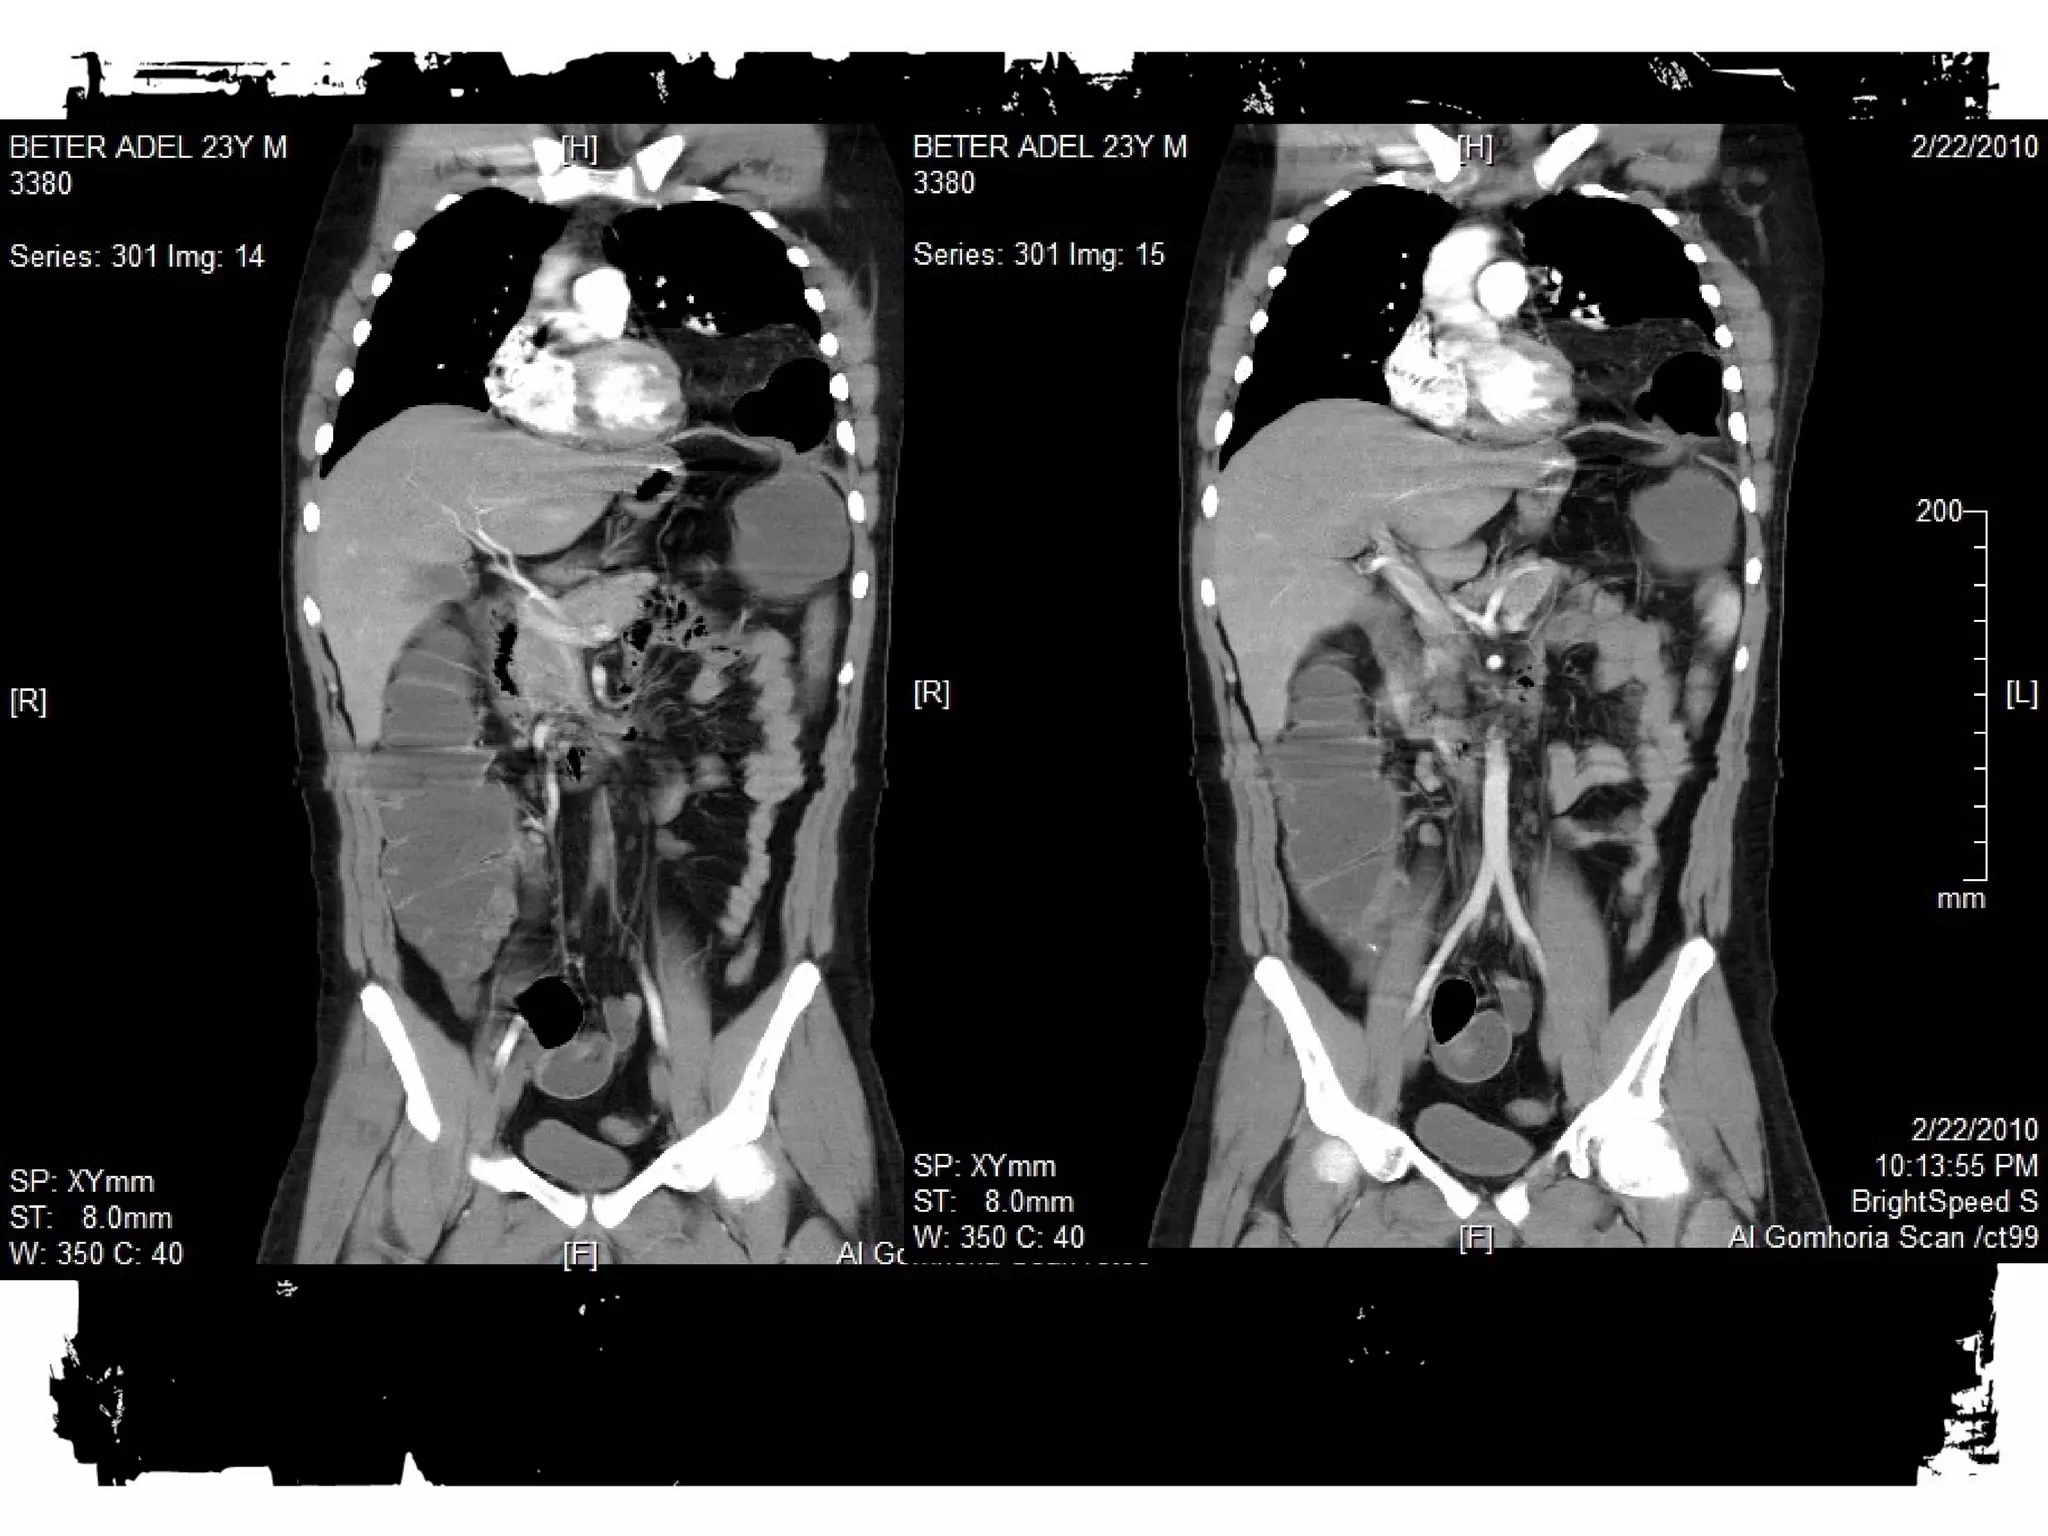

After chest trauma, imaging plays a key role for both,

the primary diagnostic work-up, and the secondary

assessment of potential treatment. Despite its well-known

limitations, the AP chest radiograph remains

the starting point of the imaging work-up. Adjunctive

imaging with CT, that recently is increasingly often

performed on MDCT units, adds essential

information not readily available on the CXR. This

allows better definition of trauma-associated thoracic

injuries not only in acute traumatic aortic injury, but

also in pulmonary, tracheobronchial, cardiac,

diaphragmal, and thoracic skeletal injuries.